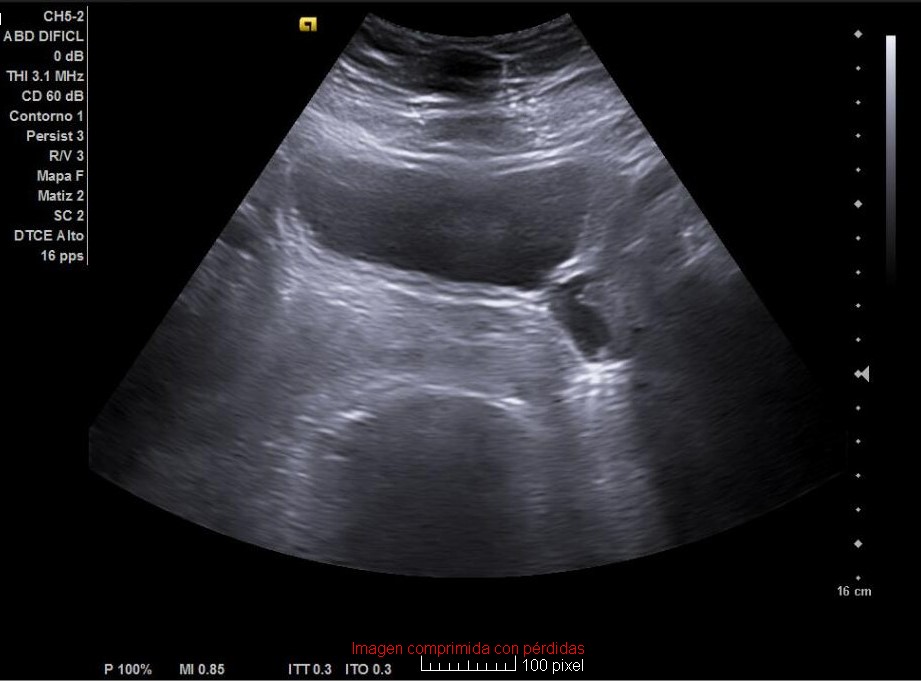

Hallazgos ecográficos

Esteatosis hepática grado I-II y además un divertículo vesical a nivel posterolateral izquierdo de 20 x 20 mm. Próstata de 22,6 cc, residuo posmiccional de 5,5 cc